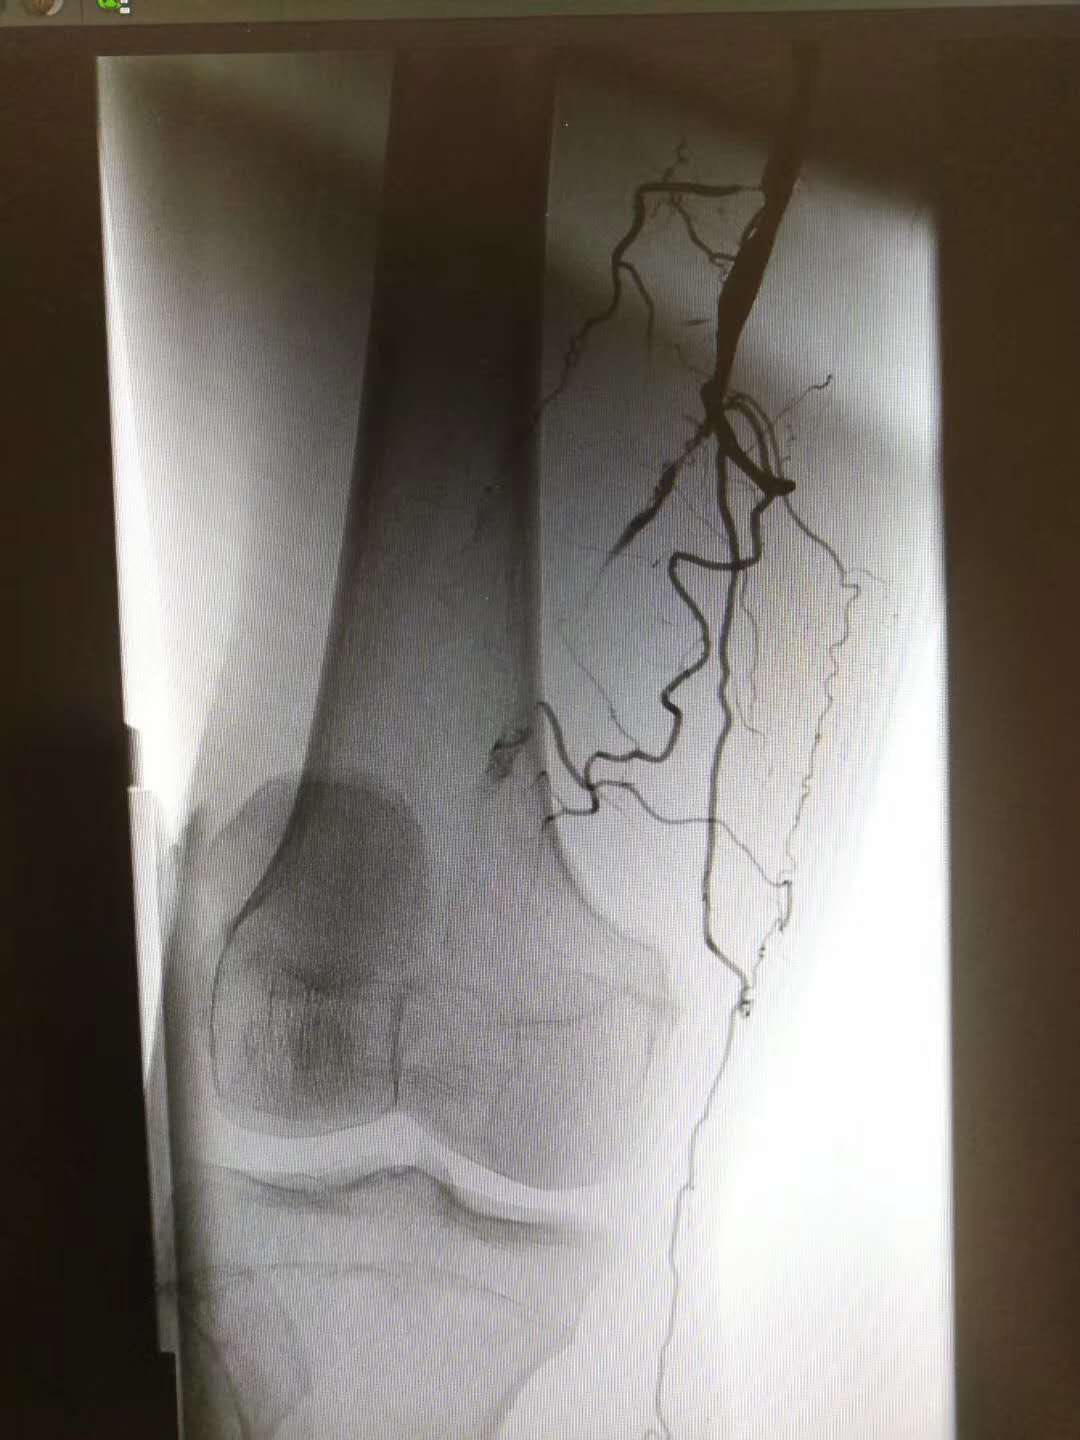

患者主因“右下肢间歇性跛行3年余”入院。通过上图术中动脉造影可以看出该患者股浅动脉近膝关节处闭塞性病变,伴有侧枝循环形成。

注:图中黑影代表在注射造影剂后血管显影情况。